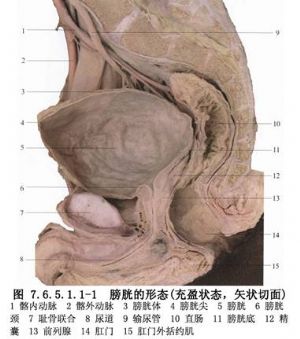

膀胱頸成管術是利用近膀胱頸的膀胱前壁組織來建立新的膀胱頸及後尿道機制。膀胱的解剖見下圖(圖7.6.5.1.1-1)。